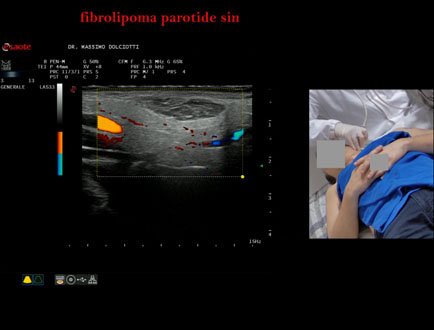

Data inserimento: 09/01/2026

Ecografia del: 22/12/2025

Strumento: Esaote MyLab Eight

Sonda: Lineare Multifrequenza 3-13 MHz

Età Paziente: M 56 anni

Motivazione dell'esame: da alcuni mesi tumefazione parotidea sinistra non dolente.

Commento all'esame: le immagini ed il video documentano formazione iso-ipoecogena, a margini definiti ma irregolari, delle dimensioni di 26 x 7 mm, senza evidenza di vascolarizzazione intra nodulare, da ricondurre, come prima ipotesi, a fibrolipoma, ma meritevole di approfondimento diagnostico.

Conclusioni: fibrolipoma parotideo sinistro (left parotid fibrolipoma).

Presentazione: Dr. Massimo Dolciotti - Ancona

Elaborazione digitale: Andrea Dini - Ancona